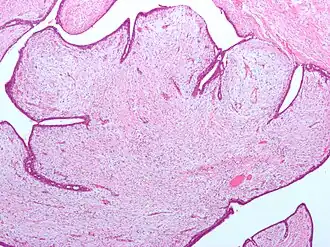

| Tumores filoides possuem grandes fendas e um estroma celular mixoide. Micrografia. Coloração H&E. | |